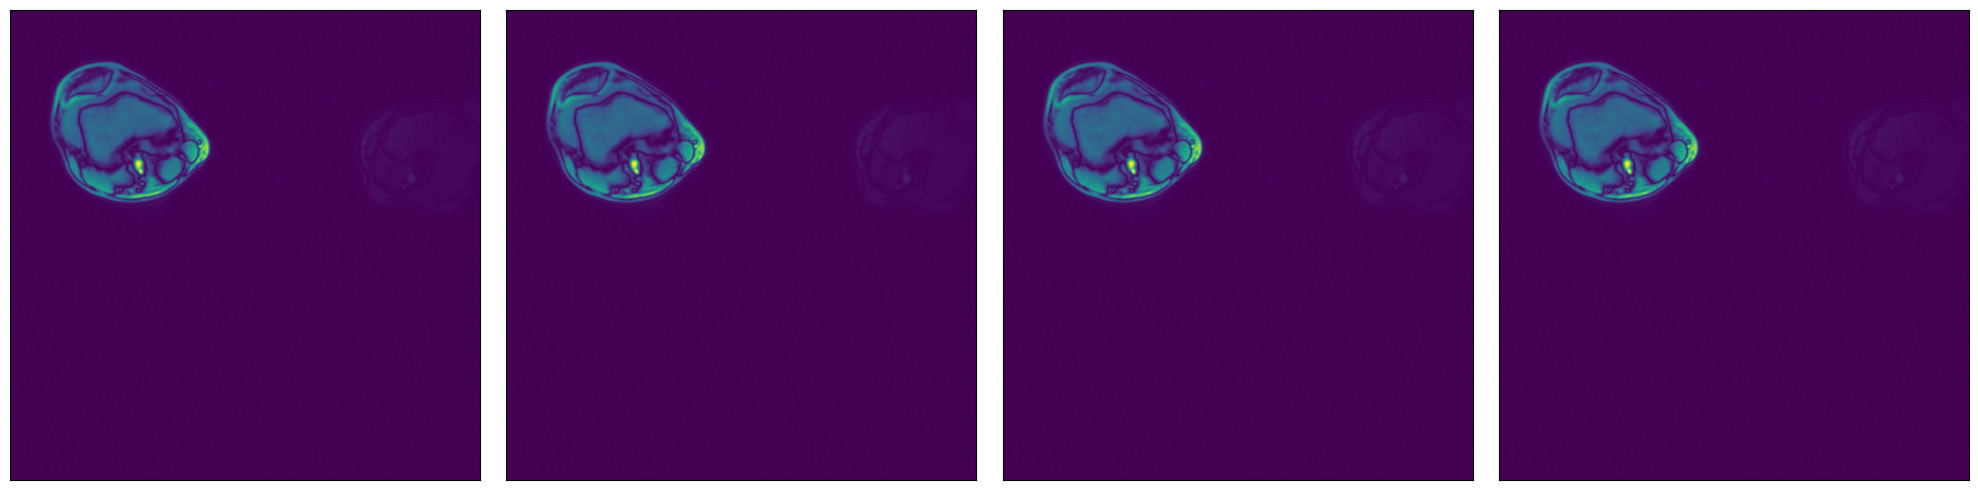

Higher dimensionality#

NumPy reader can also be used to load data of higher dimensionality (up to 6 dimensions). Let’s demonstrate with our 3D MRI arrays.

[8]:

plot_tensors(

tensor_3d[0, :, :],

tensor_3d[1, :, :],

tensor_3d[2, :, :],

tensor_3d[3, :, :],

)

Sample shape: (5, 512, 512)

../../../../_images/examples_general_data_loading_numpy_reader_dynamic_mode_16_1.png

Region-of-interest (ROI) API#

In the example shown above, we see that the relevant data is concentrated in the upper left quadrant of the image and the rest does not contain useful information. This is not true for all the images in the dataset, but it will serve us as a good example to demonstrate ROI reading.